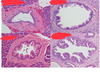

Describe the progression from GO Reflux to cancer

Firstly there’s oesophagitis due to Gastro-oesophageal reflux disease

then Barrett’s Oesophagus (metaplasia) can develop- 5% of GORD population

Dysplasia and high grade dysplasia can form

Then adenocarcinoma can develop

N.B theres’ an increased 30-100 fold risk of cancer if you have GORD

What’s the histopathology of colorectal cancer

Adenocarcinoma